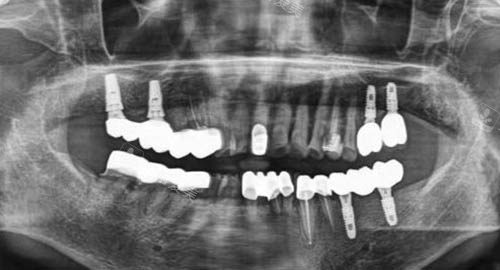

多颗牙齿种植ct

一、智能化技术助力种牙比较准度

榆林中诺口腔医院在种牙过程中运用了较高的智能化技术。

通过智能化设备,可以比较准获取患者口腔的各项数据,包括牙槽骨的密度、高度、宽度等情况。

医生能够依据这些精细的数据,为患者量身定制较适合的种植方案。

这种智能化的种牙方式,就如同给医生配备了一双“慧眼”,让每一枚植体都能比较准地植入到理想的位置,大大提高了种牙的成功概率和比较准度。